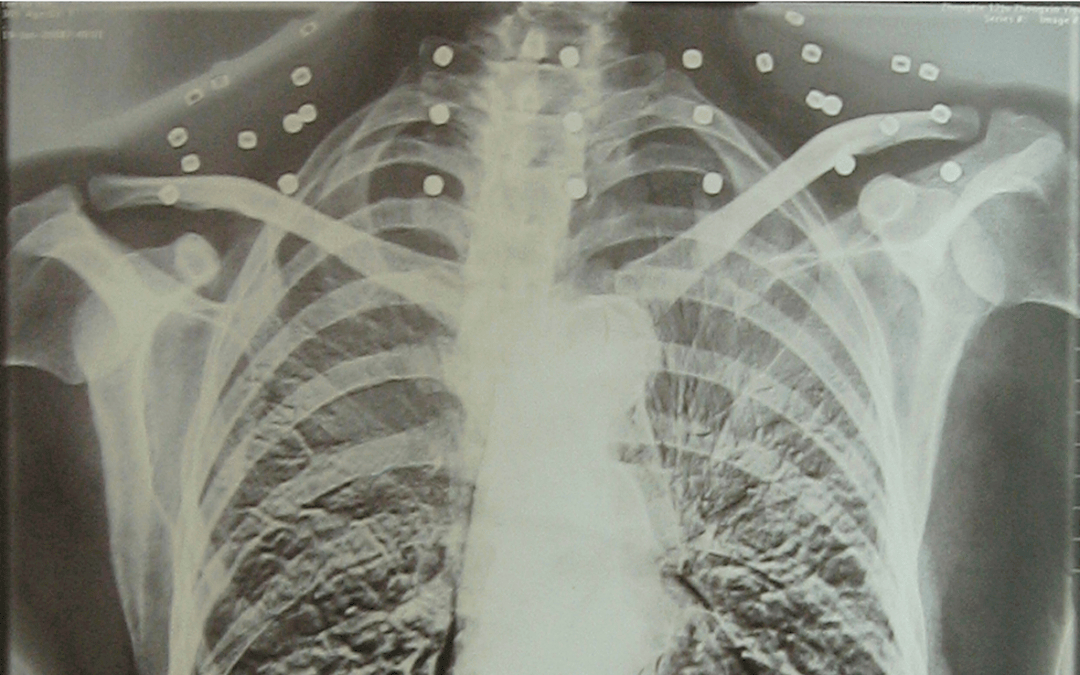

这张照片

是今年82岁的吴以先老人

拍摄的一张CT照

但实际上是

吴以先的颈部和腹部

共分布着33枚弹片

但是打进身体里的弹片

一直留在了体内

他体内的弹片都没有取出

身体留有弹片的位置就有痛感

但吴以先不考虑取出弹片

在他看来

这是他与战友并肩作战的见证

是他的勋章

与吴以先身上那33枚弹片

一起永远烙印在他心中

33枚“军功章”

是一名军人的光荣